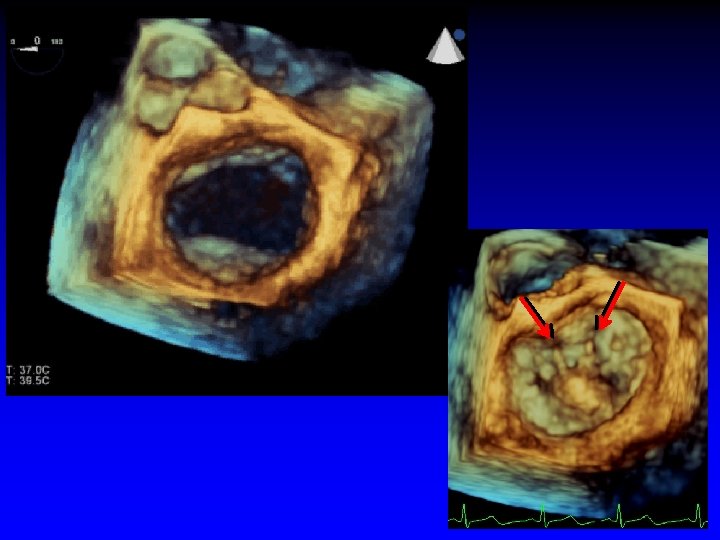

Case 1 Ruptured cords P 2

1. 6 cm +. . . + Gastric short-axis view (PSR view)

Roadmap for the surgeon

Mitral Valve Repair Information Required by Surgeon • Exact lesion(s) - affected segment(s) • Extent • Degree of calcification (leaflet/annulus) • Dilatation/size of annulus

Case 2 Ruptured cord P 2